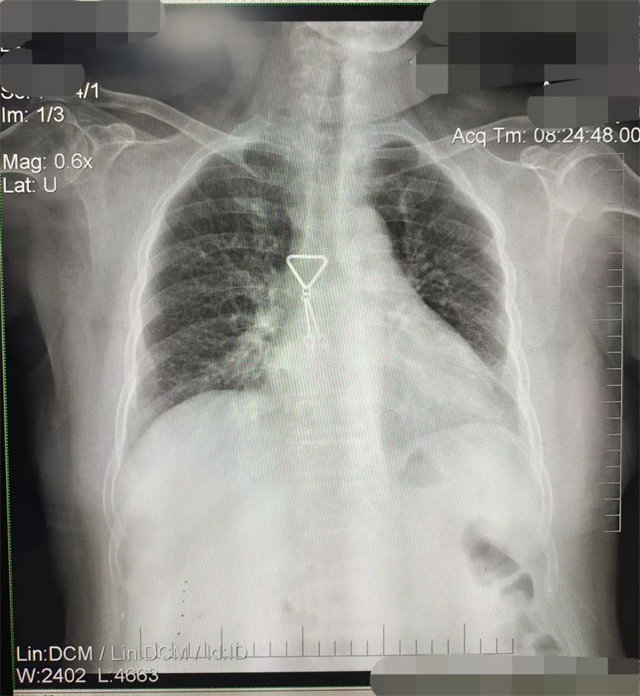

缺陷:雙側(cè)胸鎖關(guān)節(jié)不對稱,且有手機(jī)顯影。

解決:去除手機(jī)后,使患者左側(cè)緊貼成像件曝光。